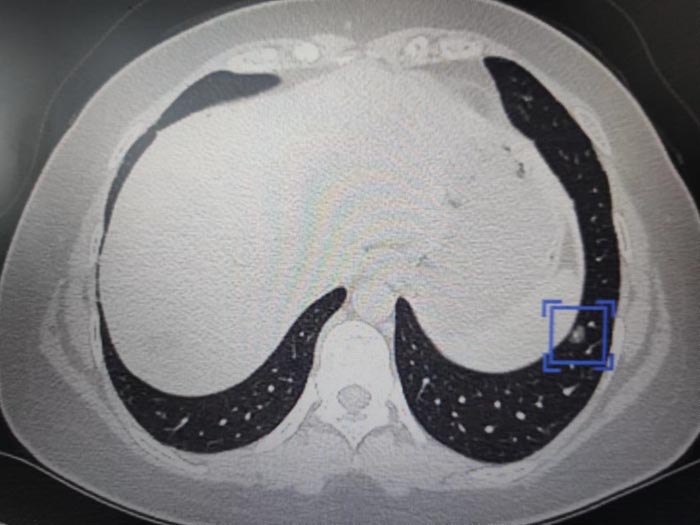

2020年小刘在体检发现肺部磨玻璃结节,医生告诉她可能是早期肿瘤,可以密切随访观察或微创手术切除。密切随访意味着要定期做胸部CT,肺部磨玻璃结节成了小刘的一块心病,想要手术,可又担心创伤大,就这样小刘每天都生活得小心翼翼。

今年,小刘再次复查,心胸外科主任医师张典钿向她详细讲解了手术的相关情况,精密详细的手术计划也让小刘下定决心,要和肺部结节做个了断,以除后患。

张典钿主任给出了答案,原来此次小刘恢复地如此迅速,主要归功于两点,第一,心胸外科多年腔镜技术经验积累,在单孔胸腔镜肺叶/肺段切除手术完全成熟的今天,可以将周围性肺结节的手术控制在半小时以内,手术时间短为小刘的快速康复打下了良好基础。创伤减少同时体现在手术切口的大小上,现在常规手术的单孔在3-4cm,而小刘的切口仅为2cm。第二,医院麻醉技术的不断更新,此次麻醉科主任、主任医师杜海靖为手术的保驾护航也起到关键作用,此次为小刘施行的是自主呼吸麻醉下的胸腔镜手术,优点包括使用喉罩辅助呼吸,不插气管插管,对声门和气管没有损伤,术后不会咽干咽痛;术中不需给予肌松药,无呼吸抑制风险;术后患者10分钟即能清醒,很快就能下地活动,自我感觉良好。此次肺结节的快速康复治疗是胸外科和麻醉科技术力量的体现,是实施患者个体化治疗的典型例子,这项技术以后将会更好的服务于肺小结节人群。

近年来,心胸外科团队针对肺部结节疾病的治疗有了一套较为成熟的体系,他们依托多学科优势,联合肿瘤科、影像科、麻醉科、病理科等多学科专家,根据肺结节影像学表现,结合患者有无吸烟、肿瘤家族史等高危因素和临床症状,进行综合评估研判,为肺结节患者制定最佳的、个体化、连续性治疗方案,以实现早期发现、准确诊断、及时处理和正确治疗的目的,帮助患者重拾健康。(心胸外科)